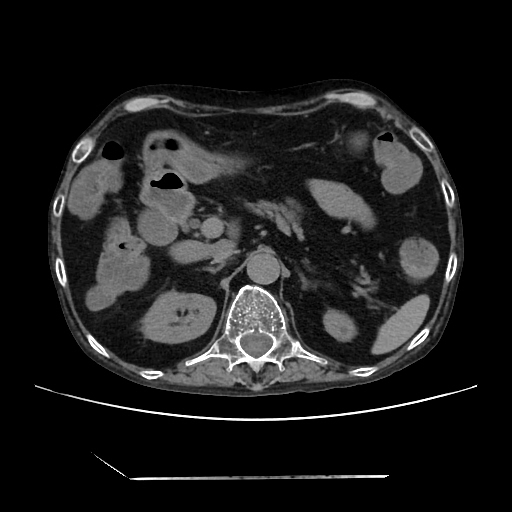

HRCT done on 17Mar16